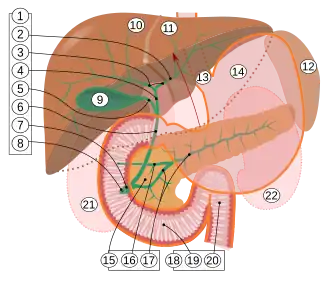

Intrahepatic bile ducts

2.

3. Left and right hepatic ducts

4. Common hepatic duct

5. Cystic duct

6. Common bile duct

7. Ampulla of Vater

8. Major duodenal papilla

9. Gallbladder

10–11. Right and left lobes of liver

12. Spleen

13. Esophagus

14. Stomach

15. Pancreas:

16. Accessory pancreatic duct

17. Pancreatic duct

18. Small intestine:

19. Duodenum

20. Jejunum

21–22. Right and left kidneys

The front border of the liver has been lifted up (brown arrow).[1]